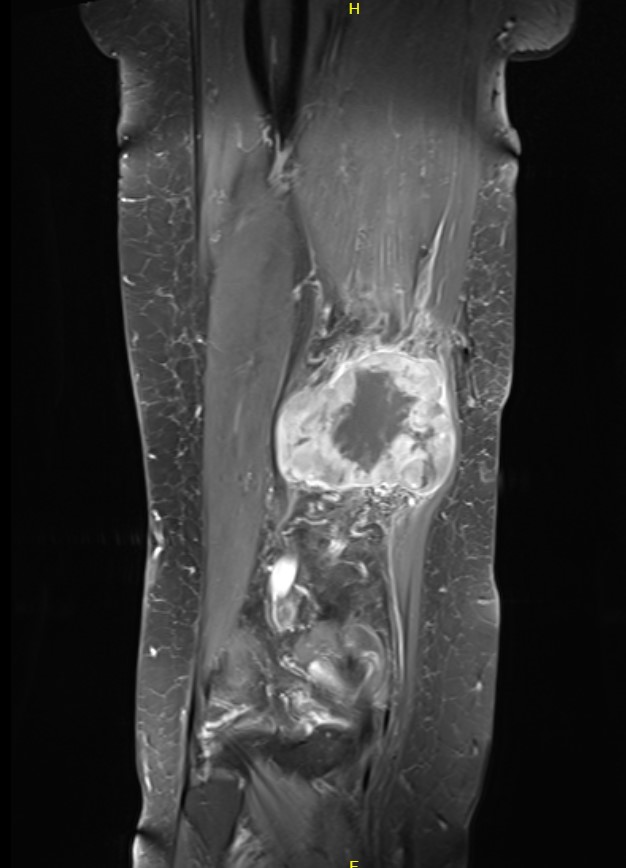

MRI

Sarcoma knee